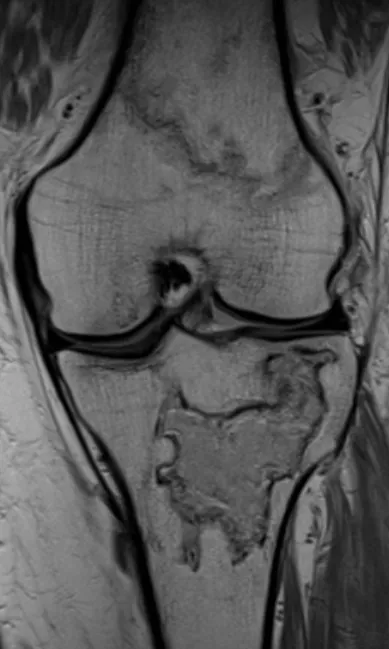

Infarct Radiology Images

Browse 2 medical images tagged with infarct. This collection includes various imaging modalities for medical education and reference.

About Infarct Imaging

This collection contains 2 radiology images related to infarct, including various imaging modalities such as X-rays, MRIs, CT scans, and ultrasound images commonly used in medical diagnosis and education.